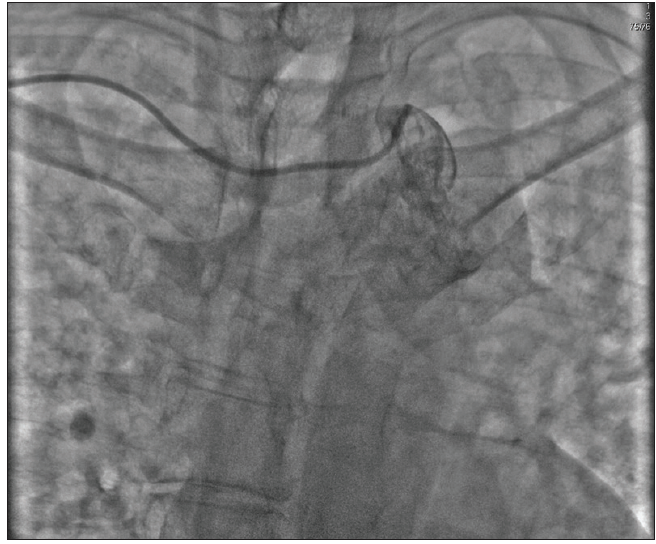

Variations in radial, brachial, and subclavian anatomy can make TR access difficult and remains the most common cause of TR access failure. It is imperative that operators are aware of different anatomic features to anticipate and overcome challenges. Tortuous forearm vessels are often difficult to negotiate with regular wires and catheters. Difficulty advancing wires or catheters is the first sign that either an anatomic variation or radial artery spasm is present, and operators should not persist or exert force that may cause vessel trauma to occur. It is important to inject from the sheath or the catheter to define the anatomy and reduce the risk of complications (Figure 1A and 1B). Most TR access with tortuosity or sharp angulations can be negotiated with a hydrophilic wire to facilitate catheter advancement. Similarly, radioulnar loops (Figure 1C) are a rare occurrence23 that may be negotiated with a hydrophilic guidewire or a standard 0.014-inch coronary wire (BMW Universal, Abbott Vascular), followed by gently advancing a 5-F catheter (Figure 1D). The use of balloon-assisted guide catheter advancement24 over a coronary guidewire (Figure 1E) is able to overcome most cases of radial tortuosity and loops. However, early switching to a femoral approach is advisable if the patient experiences discomfort or spasm.

Figure 1. Challenges in TR access and management strategies. Focal (A) and diffuse (B) radial artery spasm that did not respond to intra-arterial vasodilators. A 360° radial loop (C) that was successfully negotiated with a 5-F catheter over a hydrophilic guidewire (D). A 6-F guide catheter with a 2-mm leading balloon inflated over a coronary wire was used to successfully navigate radial artery tortuosity and spasm (E).

Figure 2. The aberrant right subclavian artery (arteria lusoria). The aberrant right subclavian origin was identified during TR access to treat a 74-year-old man for an acute anterior ST-segment elevation myocardial infarction. Due to the potential time delay associated with managing the technical difficulties of this case, alternate transfemoral access was used, and primary PCI was completed.

Subclavian tortuosity occurs more frequently in women and elderly patients,25 presenting a challenge for coronary cannulation. This can also be problematic for cases requiring multiple catheter exchanges or significant guide catheter support for equipment delivery in distal coronary segments. Access to the ascending aorta can be facilitated in most cases by asking the patient to take a deep breath, which can decrease excessive angulation between the right subclavian and the ascending aorta. If this is unsuccessful, a hydrophilic wire may be needed to negotiate the tortuosity and advance the catheter to straighten the vessel. If still unsuccessful, consider switching to the left radial artery for a more direct approach to the ascending aorta. Operators should be aware of arteria lusoria, a congenital, aberrant, retroesophageal course of the right subclavian with an aortic origin distal to the left subclavian (Figure 2). Although case reports of successful PCI in the presence of this condition have been reported,26 we find that treating these patients via the right TR access is a challenge, and early switching to a left radial or a femoral approach is advised.